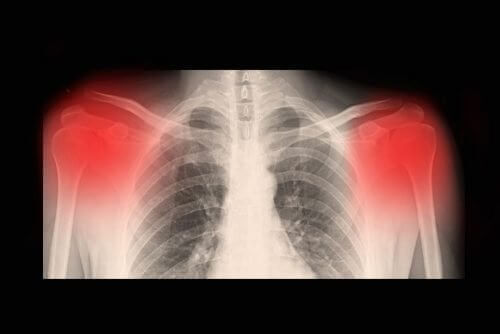

Обикновено диагнозата се поставя след извършване на редица изследвания. Най-често това става след рентгеново изследване, компютърна томография или ЯМР. Нивото на прогресиране на болестта може да бъде установено и чрез ехограф с висока резолюция.